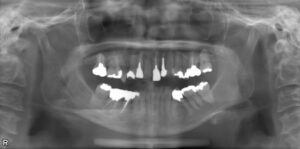

• 上下臼歯9本欠損症例

BEFORE AFTER 74歳女性/上下9本欠損/インプラント埋込手術 【治療内容】 根っこの先で炎症が広がり抜歯とな…